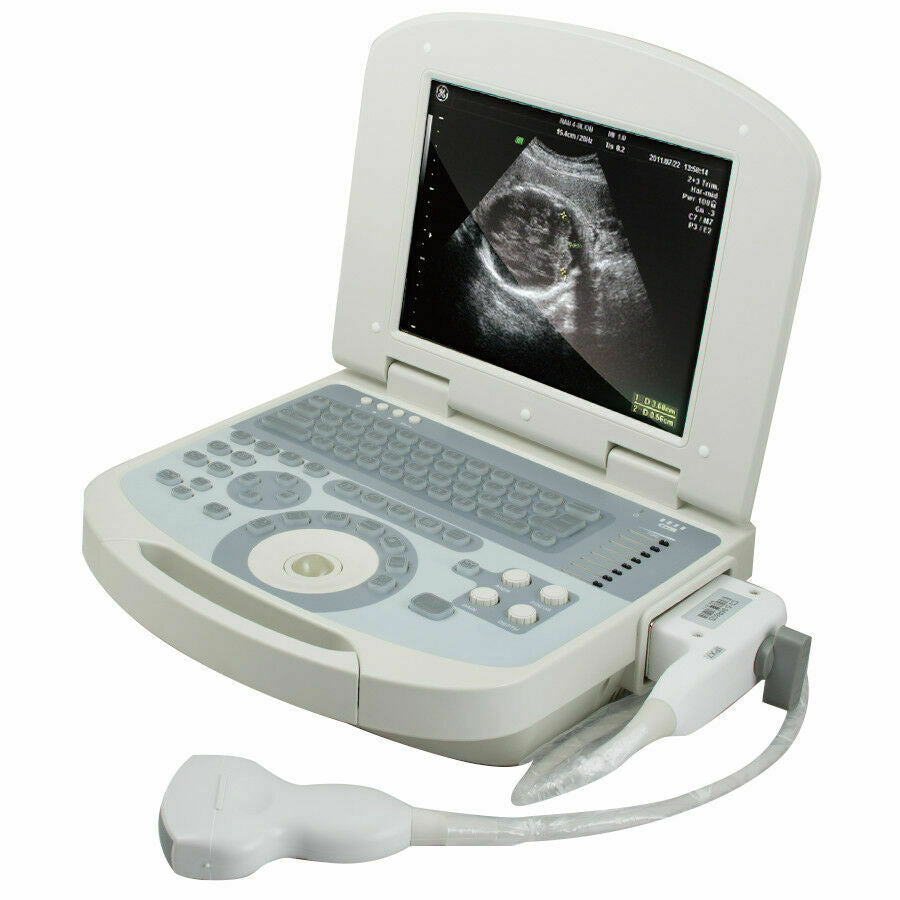

The New Portable Notebook Digital Laptop Machine Ultrasound Scanner is a groundbreaking device that has revolutionized the field of portable diagnostic imaging. With its advanced features and lightweight design, it is an ideal tool for medical professionals who need to perform ultrasound scans in various settings. This remarkable machine combines cutting-edge technology with convenience, making it an essential addition to any healthcare provider's toolkit.

Designed with portability and functionality in mind, the New Portable Notebook Digital Laptop Machine offers superior performance without compromising on ease of use. Its compact size allows for easy transport and setup, while the digital laptop interface ensures that users can quickly access and utilize the scanner's capabilities. The inclusion of a convex probe and 3D imaging further enhances the diagnostic accuracy, providing clearer and more detailed images than ever before.

One of the key advantages of this ultrasound scanner is its versatility. It can be used in a wide range of medical scenarios, including emergency rooms, ambulances, and remote clinics. The New Portable Notebook Digital Laptop Machine is particularly valuable in situations where traditional, bulky ultrasound machines would be impractical. Because of its battery-operated design and robust construction, it can withstand the demands of frequent use in diverse environments.

Overall, the New Portable Notebook Digital Laptop Machine with Ultrasound Scanner and Convex Probe+3D is a state-of-the-art tool that embodies innovation, portability, and efficiency. It empowers medical professionals to provide high-quality care in various scenarios and enhances the overall diagnostic process. Investing in this advanced ultrasound machine is a step towards improving patient outcomes and expanding the capabilities of ultrasound imaging in modern medicine.